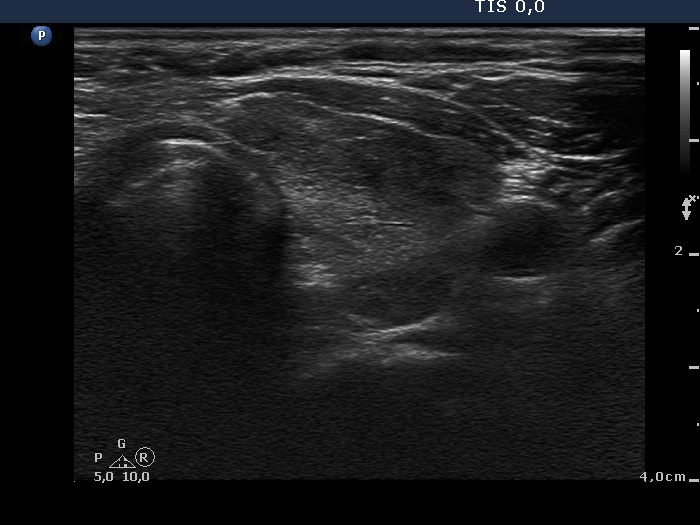

Fourth examination 21 months after initial investigation (fourth and fifth rows):

Clinical presentation: The patient requested a second opinion. Multiple nodules including a suspicious one in the right lobe were described in another institute. Scintigraphy diagnosed multiple "cold" and warm" nodules in both lobes. Surgery was advised. The surgeon asked aspiration cytology of the hypoechogenic nodule described as suspicious on ultrasonography.

Palpation: unchanged.

Results of blood tests: euthyroidism on daily 25 mg methimazole (TSH 3.78 mIU/L, FT4 10.9 pM/L).

Ultrasonography: unchanged.Cytology was performed from the hypoechogenic area in the upper part of the right thyroid.

Cytological diagnosis: benign pattern corresponding to previous dysfunction and isotope therapy.

The patient underwent total thyroidectomy. Histopathology disclosed diffuse goiter corresponding to Graves' disease and focal lymphocytic thyroiditis. There were no nodules.

Comment. It is worth analyzing the echo pattern of the thyroid. The small hypoechogenic area in the right lobe changed neither in size nor is shape nor in vascularization over 11 months.